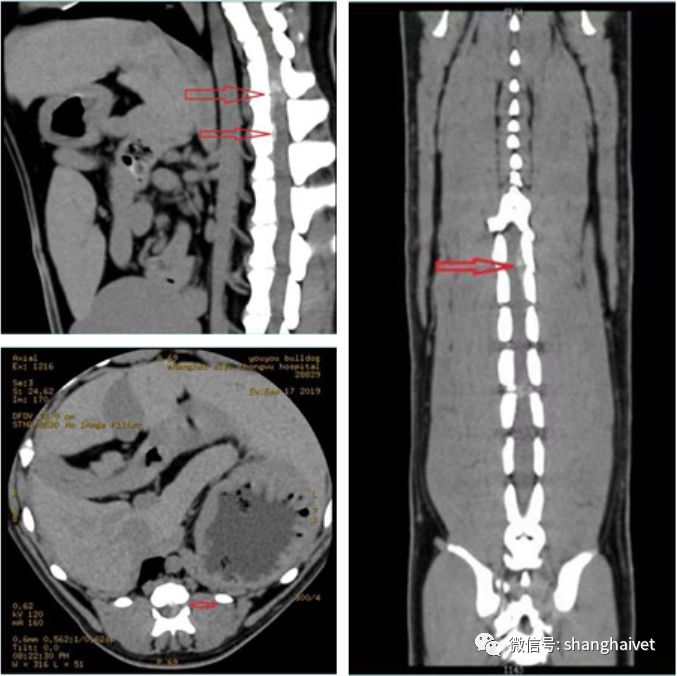

▲CT扫描结果

CT显示,悠悠胸腰椎椎间隙明显狭窄,在最后一节胸椎和第一节腰椎即13胸椎和第1腰椎之间以及第1和2腰椎之间有明显的矿化椎间盘物质突出,虽然突出物量少,但是动能大,突然释放进入椎孔,对脊髓造成了严重的冲击,因此悠悠表现出无法走路的症状。影像上呈雾状的高密度影像为脊髓受冲击后的出血表现。